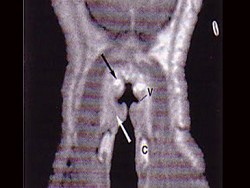

11.MRI檢查結果如下圖,下一步最重要的檢查是  (    )

12.本患者最可能的診斷是  (    )

13.如果碘同位素檢查示舌根腫物有核素聚焦,而頸部無核素聚焦,正確的治療是  (    )

正確答案:11.C;12.C;13.A